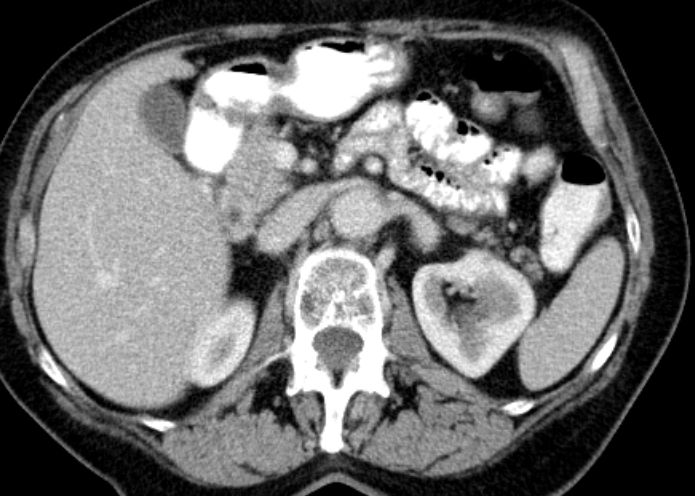

| Cholestase | 78-jährige Frau mit Pankreaskopfkarzinom. Die intrahepatischen Gallenwege sind stark erweitert.![]() |

Gallenblasenhydrops. Die kontrastierten Leberarterien verlaufen parallel zu den Gallenwegen.![]() |